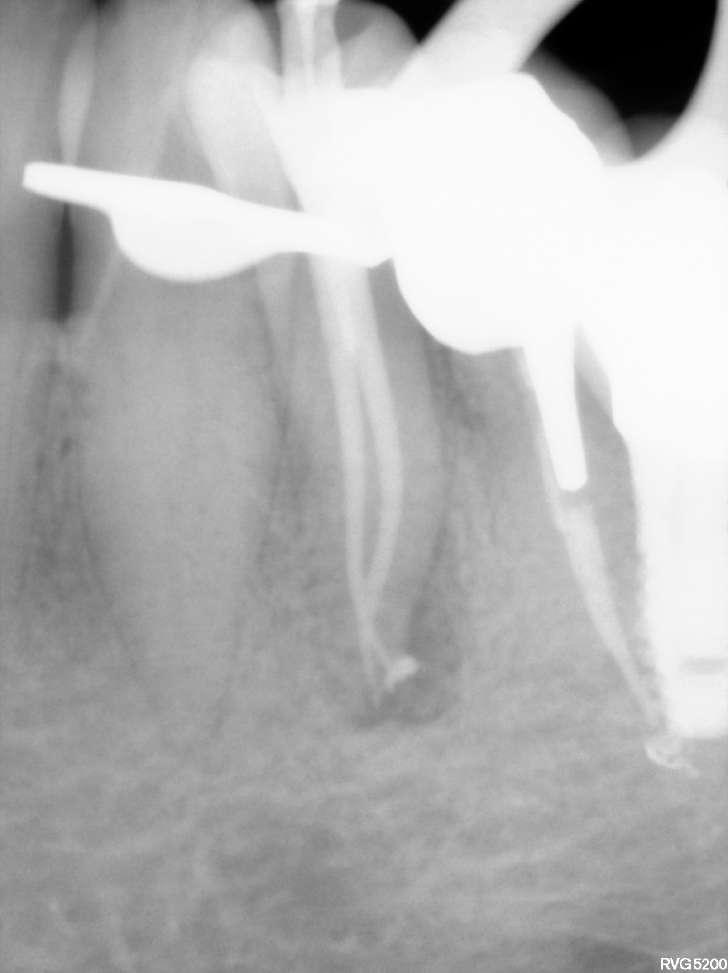

Wenn man sich dieses präoperative Röntgenbild ansieht, sind zwei Hinweise zu diesem endodontischen Fall zu erkennen (Abb. 1): Obliteration der Pulpakammer und enge Kanäle Ungewöhnliche Anatomie der distalen Wurzel

Mit hochtourigen Diamantbohrern wurde eine konventionelle Zugangskavität angelegt und die drei Öffnungen wurden mit Ultraschallspitzen lokalisiert. Die KFeile #08 wurde verwendet, um das endodontische System aller Wurzeln zu erkunden, wobei aber der Apex im distalen Kanal nicht erreicht werden konnte. Das Aufweiten und die Instrumentierung im mittleren Drittel erfolgten mit einer reziprok arbeitenden kleinen (gelben) EdgeOne-Feile (Edge Endo, Albuquerque, NM), die mit Einwärts-Auswärts-Bewegungen von 1-2 mm im Wechsel mit bürstenden Bewegungen zum koronalen Erweitern der Kanäle verwendet wurde. Es wurde eine regelmäßige und reichliche manuelle Spülung mit Lösungen von 5% Natriumhypochlorit durchgeführt. Nach der Aufbereitung des koronalen und mittleren Teils wurde die Arbeitslänge mit der K-Feile #10 bestimmt und das Aufbereitungsverfahren mit martensitischen X7-Instrumenten (Edge Endo, Albuquerque, NM) in den Größen 17 und 25, Konizität .04 abgeschlossen. Die Instrumente wurden mit reziproker Rotation im Uhrzeigersinn (150°-30°) verwendet, um die Torsions- und Biegebelastung zu verringern (Abb. 2).

FALLBERICHT: Abb.1 Abb.2